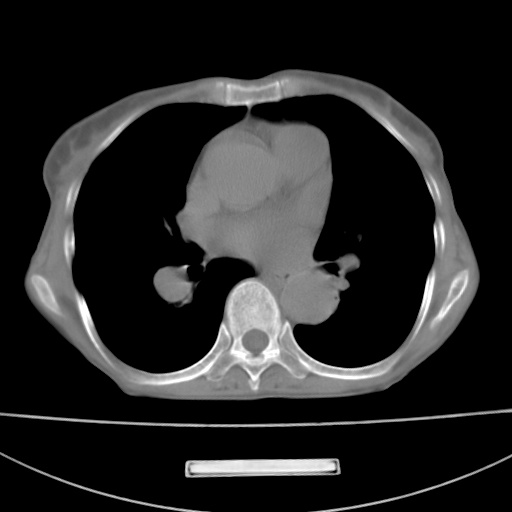

患者 女 67岁,反复咳嗽咳痰2年,加重伴喘及双下肢浮肿1月

陈旧性肺结核、慢性支气管炎、支气管扩张症、肺心症、肺动脉高压。

诸大血管及f肺门血管增粗迂曲.左下肺多发薄壁空腔影.部分非也透亮度增高.薄曾扫描可区分肺气肿类型.考虑1.慢性支气管炎 2.左下肺支气管扩张 3.肺气肿 4 肺动脉高压5.是否有先心病病史

支扩,肺动脉高压